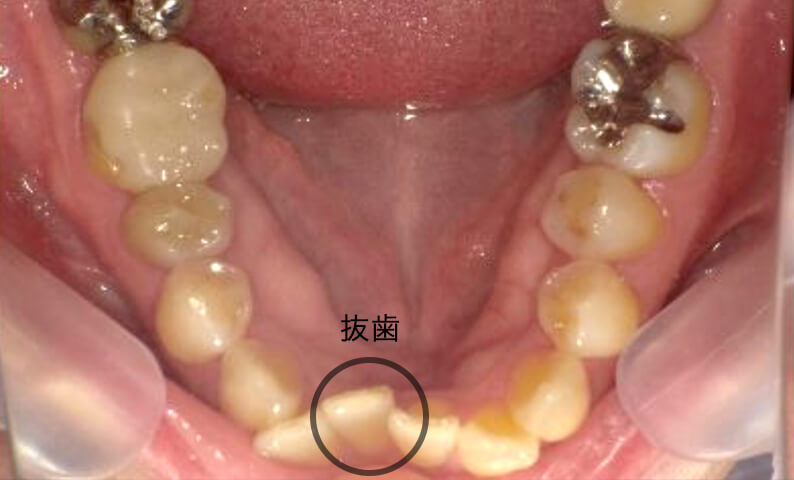

症例_001 下顎だけの部分矯正

治療期間:8ヶ月金額:21万円+税女性前歯のガタガタ下の前歯だけ

| Before | After |